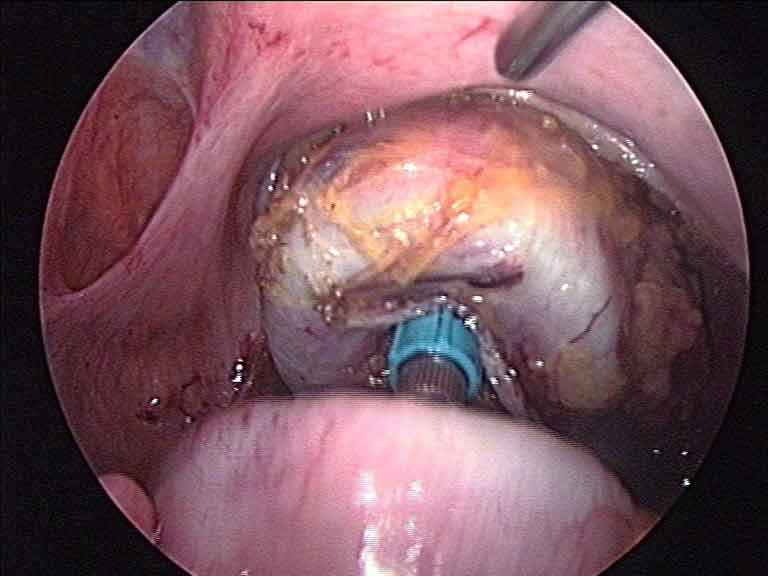

Laparoscopic inguinal hernia repair — TEP mesh placement in groin

Inguinal (Groin) Hernia

Laparoscopic Inguinal Hernia Surgery

Keyhole repair of groin hernias using the TEP (totally extra-peritoneal) or TAPP (trans-abdominal pre-peritoneal) technique. A mesh is placed laparoscopically to close the defect — with less post-operative discomfort and typically a faster return to normal activity.